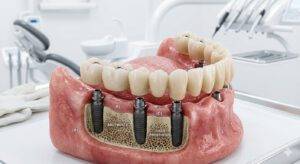

A prótese protocolo sobre implantes é uma das soluções mais modernas da implantodontia para pacientes que perderam todos os dentes de uma arcada. Diferente das dentaduras removíveis tradicionais, o protocolo é uma prótese fixa apoiada em implantes dentários, oferecendo maior estabilidade, conforto e segurança.

A prótese protocolo é uma prótese fixa instalada sobre implantes dentários para substituir todos os dentes de uma arcada, seja superior (maxila) ou inferior (mandíbula).

Normalmente são instalados 4 a 6 implantes dentários, que servem como base para sustentar uma prótese completa fixa.

Após a instalação dos implantes dentários, a prótese protocolo é confeccionada e fixada sobre eles, devolvendo estética, função e estabilidade ao sorriso do paciente.

Tipos de prótese protocolo sobre implantes

Existem diferentes materiais utilizados na confecção da prótese protocolo. Os três principais são:

- protocolo acrílico

- protocolo metalocerâmico

- protocolo em zircônia

Cada material possui características específicas relacionadas à estética, resistência e durabilidade.